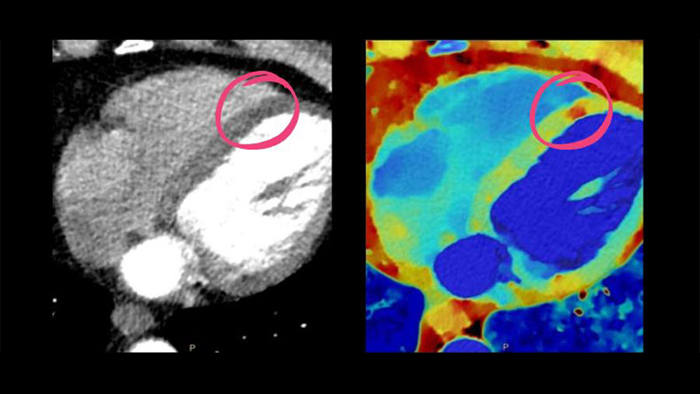

See beyond routine cardiac imaging with the additional clinical information of Spectral CT for advanced cardiac applications. Learn how the Spectral CT 7500's "Always On" Spectral CT workflow helps you meet the needs of all your patients with zero compromises.

Unlock the full potential of CT as a non-invasive cardiac diagnostic tool.